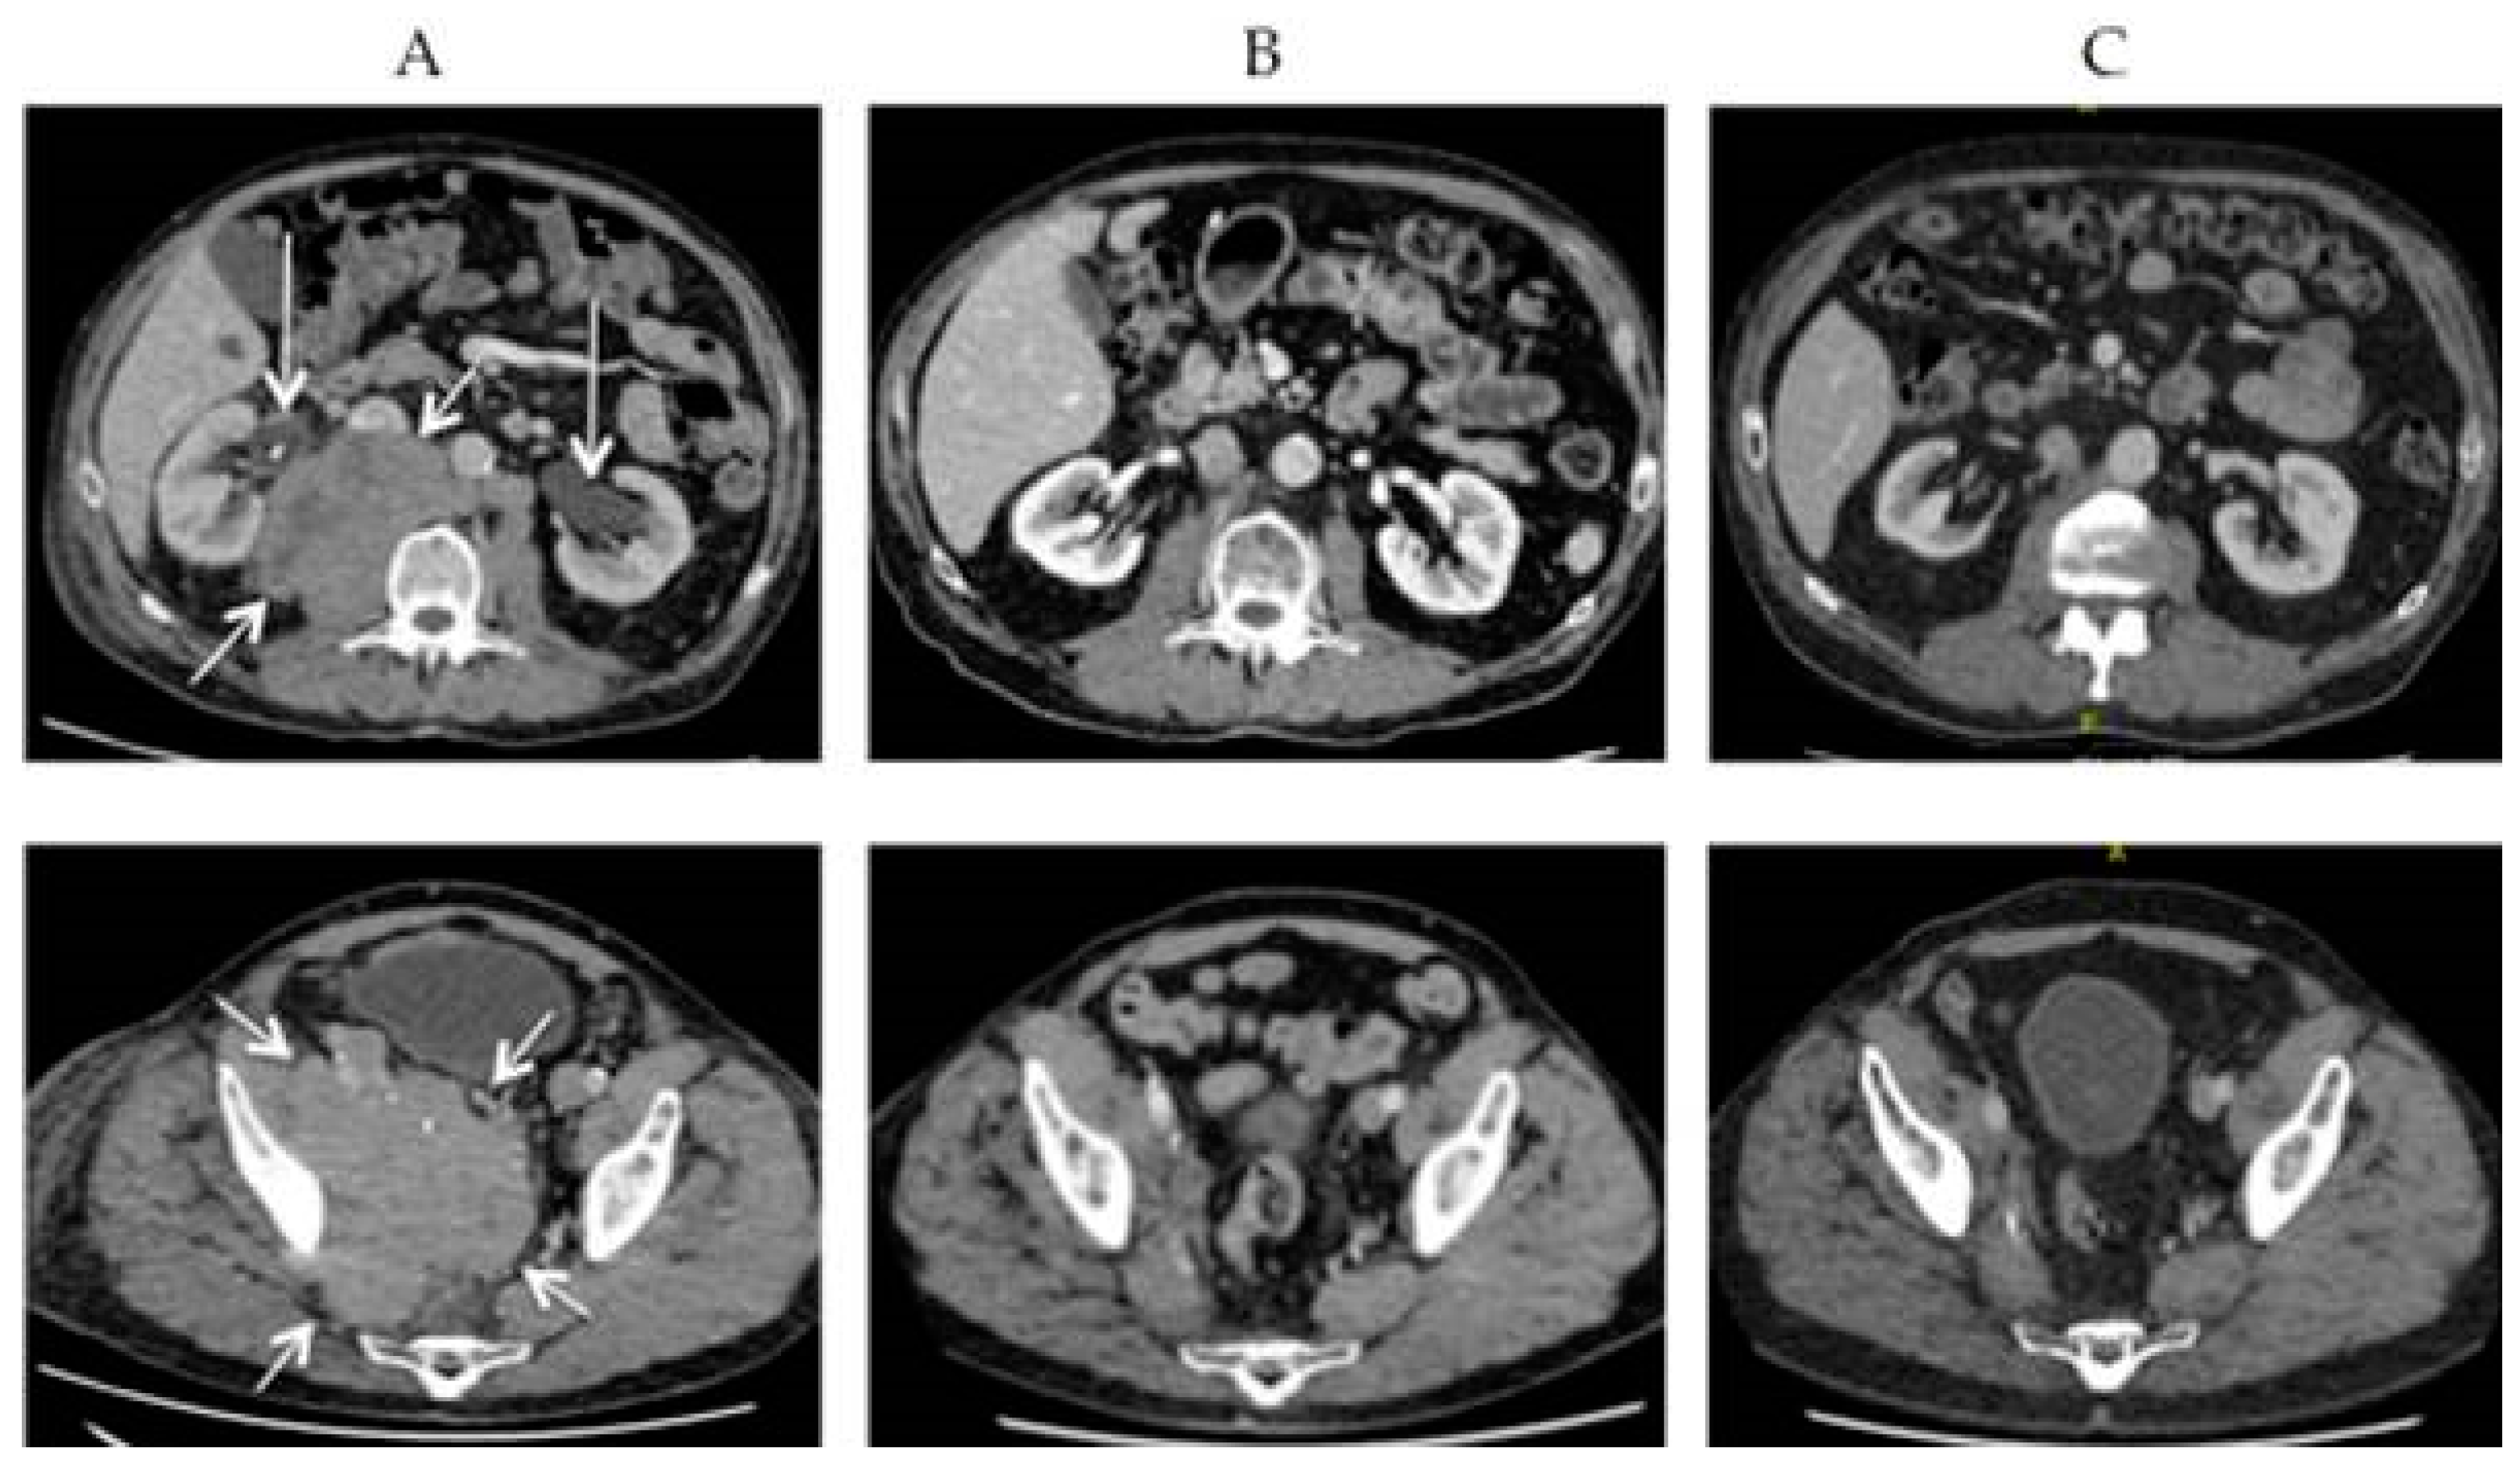

- Singh, N.; Alexander, N.A.; Lachance, K.; Lewis, C.W.; McEvoy, A.; Akaike, G.; Byrd, D.; Behnia, S.; Bhatia, S.; Paulson, K.G.; et al. Clinical benefit of baseline imaging in Merkel cell carcinoma: Analysis of 584 patients. J. Am. Acad. Dermatol. 2021, 84, 330–339. [Google Scholar] [CrossRef]

- Sachpekidis, C.; Sidiropoulou, P.; Hassel, J.C.; Drakoulis, N.; Dimitrakopoulou-Strauss, A. Positron emission tomography in Merkel cell carcinoma. Cancers 2020, 12, 2897. [Google Scholar] [CrossRef] [PubMed]